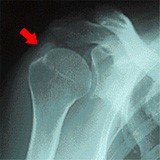

石灰沈着性腱板炎では、何もしていないのに突然、腕を動かすことも、触れることも出来ないほどの激痛が肩に現れます。原因は肩の深層筋(腱板)に付着した石灰が、関節を包む袋を突き破ったために起きた炎症です。打身や外傷がなく、無理に動かしたわけでもないのに、突発的な激痛があれば、石灰沈着性腱板炎を疑います。

他の肩の疾患と症状が似ている為、誤って診断されることがあります。五十肩とは症状が似ていますが、レントゲン撮影で石灰沈着があれば、鑑別することが出来ます。腱板損傷では、痛みのある部位と、肩関節の動きを見て鑑別することが出来ます。